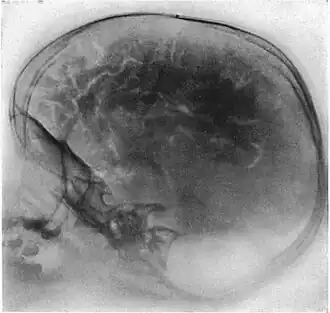

Pneumoencephalography (sometimes abbreviated PEG; also referred to as an "air study") was a common medical procedure in which most of the cerebrospinal fluid (CSF) was drained from around the brain by means of a lumbar puncture and replaced with air, oxygen, or helium to allow the structure of the brain to show up more clearly on an X-ray image. It was derived from ventriculography, an earlier and more primitive method in which the air is injected through holes drilled in the skull.

Pneumoencephalography makes use of plain X-ray images. These are very poor at resolving soft tissues, such as the brain. Moreover, all the structures captured in the image are superimposed on top of each other, which makes it difficult to pick out individual items of interest (unlike modern scanners, which are able to produce fine virtual slices of the body, including of soft tissues). Therefore, pneumoencephalography did not usually image abnormalities directly; rather, their secondary effects. The overall structure of the brain contains crevices and cavities that are filled by the CSF. Both the brain and the CSF produce similar signals on an X-ray image. However, draining the CSF allows for greater contrast between the brain matter and the (now drained) crevices in and around it, which then show up as dark shadows on the X-ray image. The aim of pneumoencephalography is to outline these shadow-forming air-filled structures so that their shape and anatomical location can be examined. Following the procedure, an experienced radiologist reviews the X-ray films to see if the shape or location of these structures have been distorted or shifted by the presence of certain kinds of lesions. This also means that in order to show up on the images, lesions have to either be located right on the edge of the structures or if located elsewhere in the brain, be large enough to push on surrounding healthy tissues to an extent necessary to cause a distortion in the shape of the more distant air-filled cavities (and hence more-distant tumors detected this way tended to be fairly large).